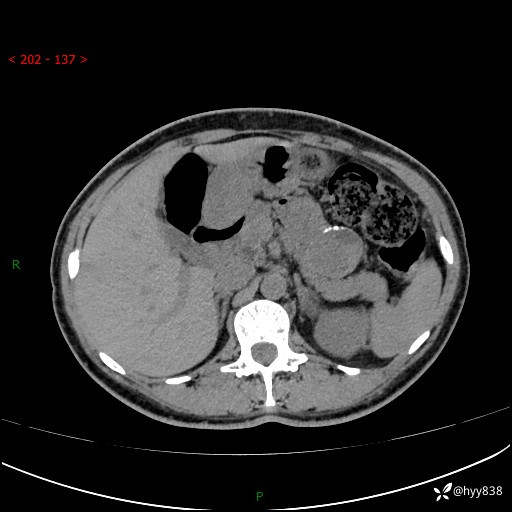

胰腺CT平扫

img